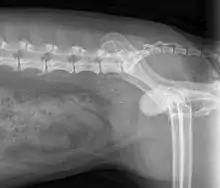

| X-Ray | ![]() An example of an X-ray from a dog. |